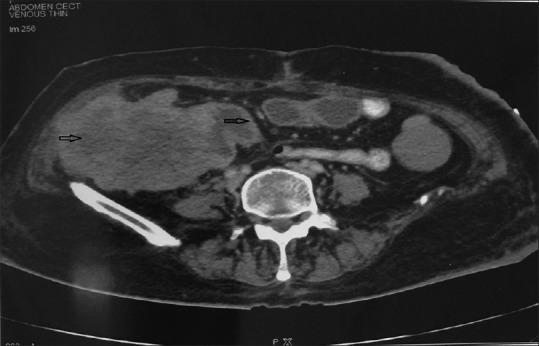

A total of 31 biopsy proven patients showing variable bowel wall thickening involving the colon /rectum on CECT (Contrast Enhanced Computed Tomography) were included in the study. The tumours were staged based on the CT scan findings and were compared with the operative and histopathological findings.

Rectum was the most common site of involvement followed by the recto-sigmoid involvement. Metastasis was observed in 5 cases out of the 31 malignant cases. Five of the 7 cases were correctly staged as T1 & T2 lesions on CT having a sensitivity of 83.3%, specificity of 92%, and positive predictive value of 71.4% and a negative predictive value of 95.8% in the diagnosis of T1 and T2 lesions. 15 of the 16 cases were correctly staged as T3 lesions. CT had a sensitivity of 88.2%, specificity of 93.8%, and positive predictive value of 93.8% and a negative predictive value of 86.7% in the diagnosis of T3 lesions. All the 8 cases were correctly staged as T4 lesions. CT had a sensitivity of 100%, specificity of 100%, and positive predictive value of 100% and a negative predictive value of 100% in the diagnosis of T4 lesions.

本研究纳入了31例经活检证实、在对比增强计算机断层扫描(CECT)上显示结肠/直肠肠壁增厚情况各异的患者。根据CT扫描结果对肿瘤进行分期,并与手术及组织病理学结果进行比较。

直肠是最常受累的部位,其次是直肠乙状结肠交界处受累。31例恶性病例中有5例出现转移。7例中的5例在CT上被正确分期为T1和T2病变,在诊断T1和T2病变时,敏感性为83.3%,特异性为92%,阳性预测值为71.4%,阴性预测值为95.8%。16例中的15例被正确分期为T3病变。CT在诊断T3病变时,敏感性为88.2%,特异性为93.8%,阳性预测值为93.8%,阴性预测值为86.7%。所有8例均被正确分期为T4病变。CT在诊断T4病变时,敏感性为100%,特异性为100%,阳性预测值为100%,阴性预测值为100%。